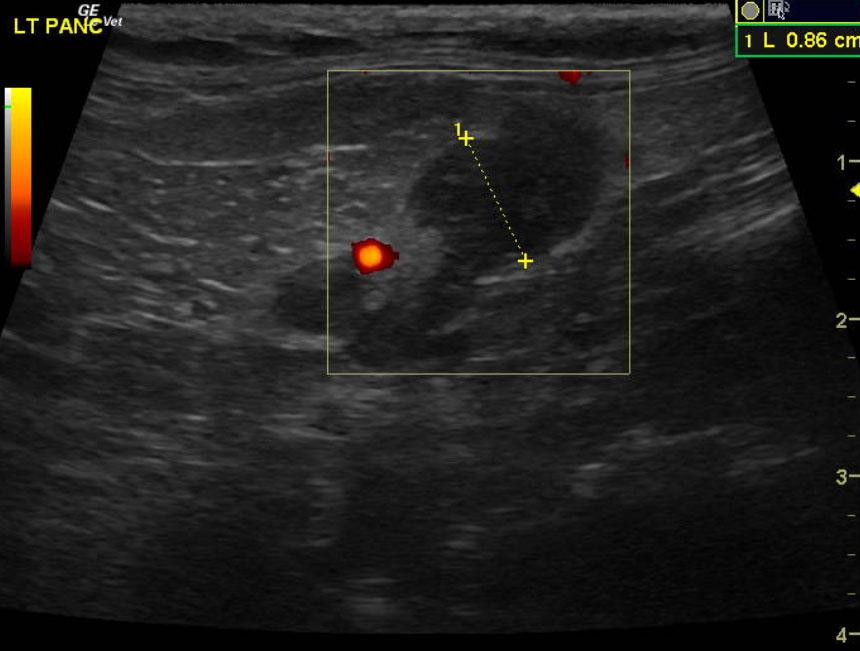

A 15-year-old MN DMH cat was presented for chronic diarrhea, hyperthyroid, dehydration, otitis externa, and periodontal disease. The CBC was markedly normal with blood chemistry revealing an elevated ALT (154,) elevated SAP (109,) hyperT4 (>10,). An IDEXX feline diarrhea panel was negative for virus, parasites, & bacteria.